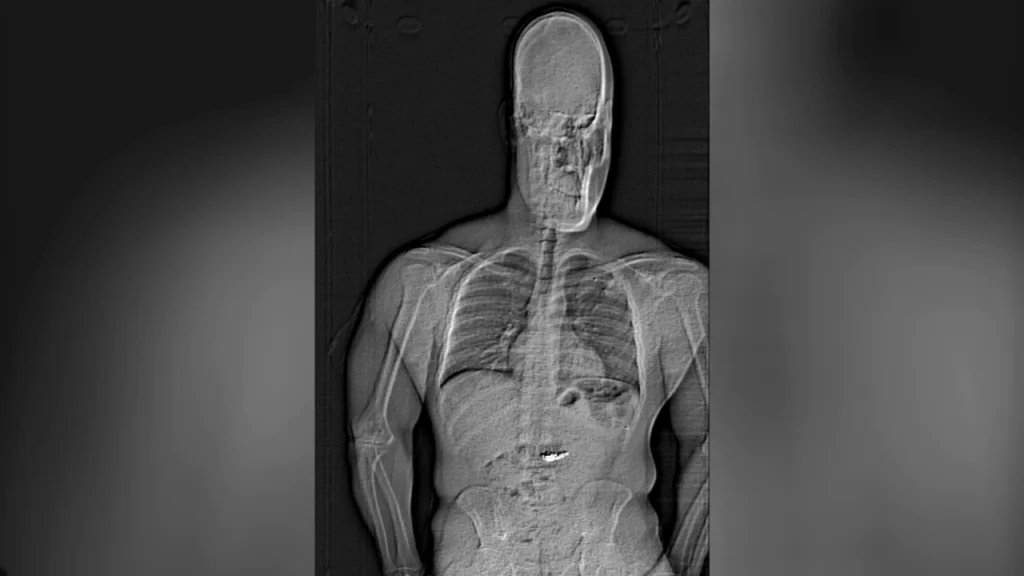

X-ray shows diamond earrings swallowed by theft suspect during arrest, police say:​

A suspected thief gulped down two pairs of diamond earrings during his arrest on the side of a Florida Panhandle highway last week, detectives say, leaving them with the unenviable task of waiting to "collect" the Tiffany & Co. jewelry worth nearly $770,000.

"These foreign objects are suspected to be the Tiffany earrings taken in the robbery but will need to be collected ... after they are passed," the department's arrest report said.